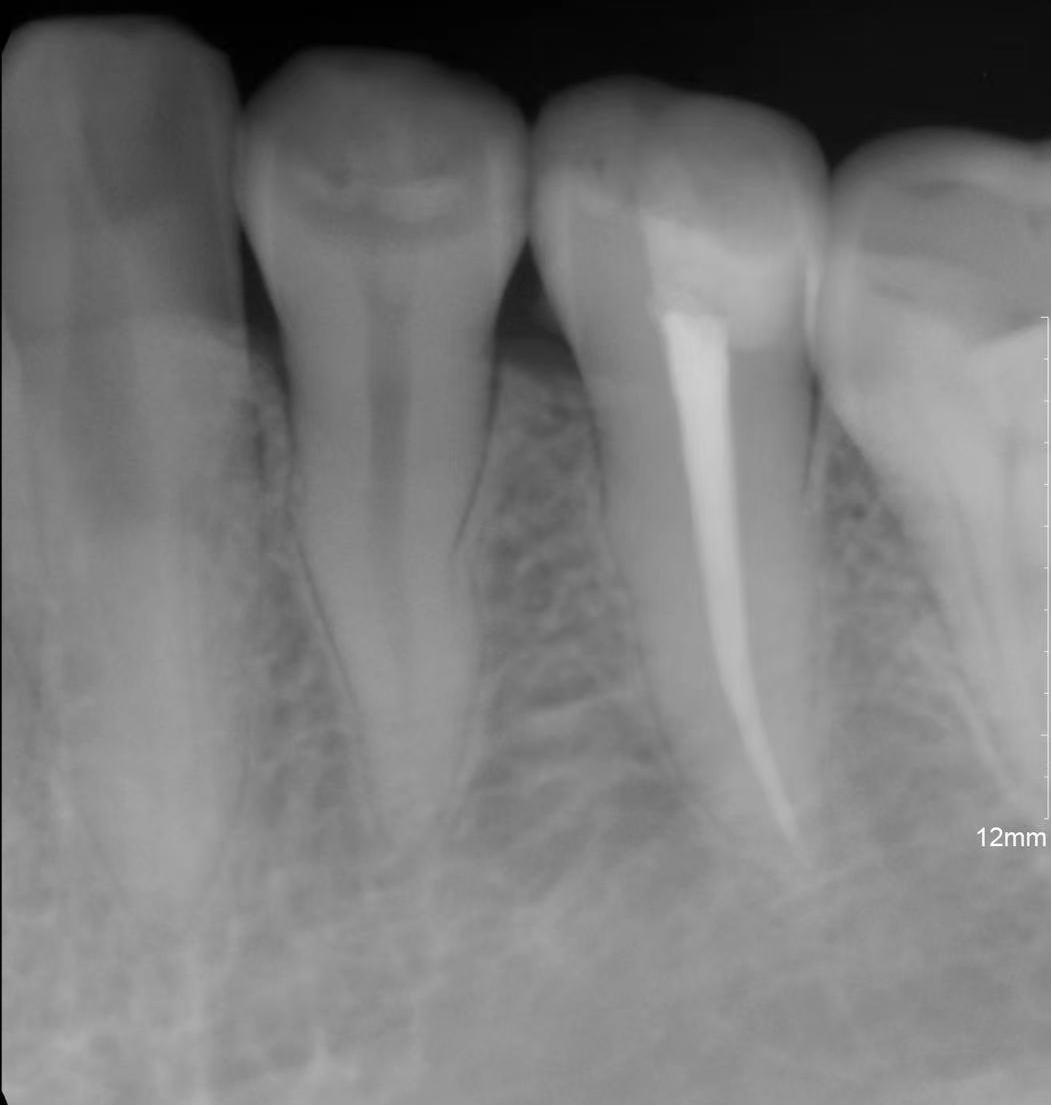

必要时可自窦道口插入诊断丝

拍摄X线示踪片以确定窦道的来源。

( 根管治疗前后对比图)